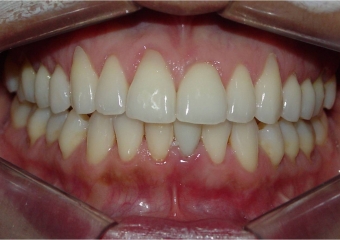

Raio x após extração e instalação do implante e dente provisório imediato

Imagens do dente provisório fixo imediato, no implante Cone Morse Facility